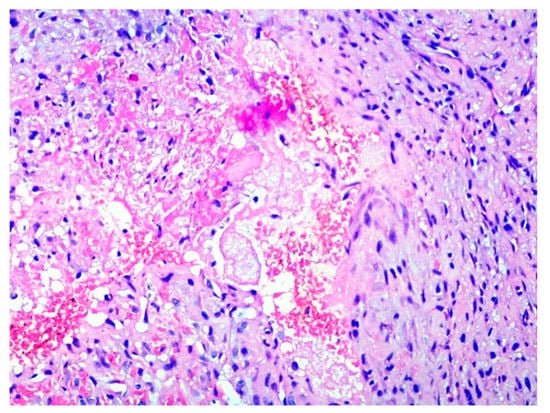

2. Case Presentation